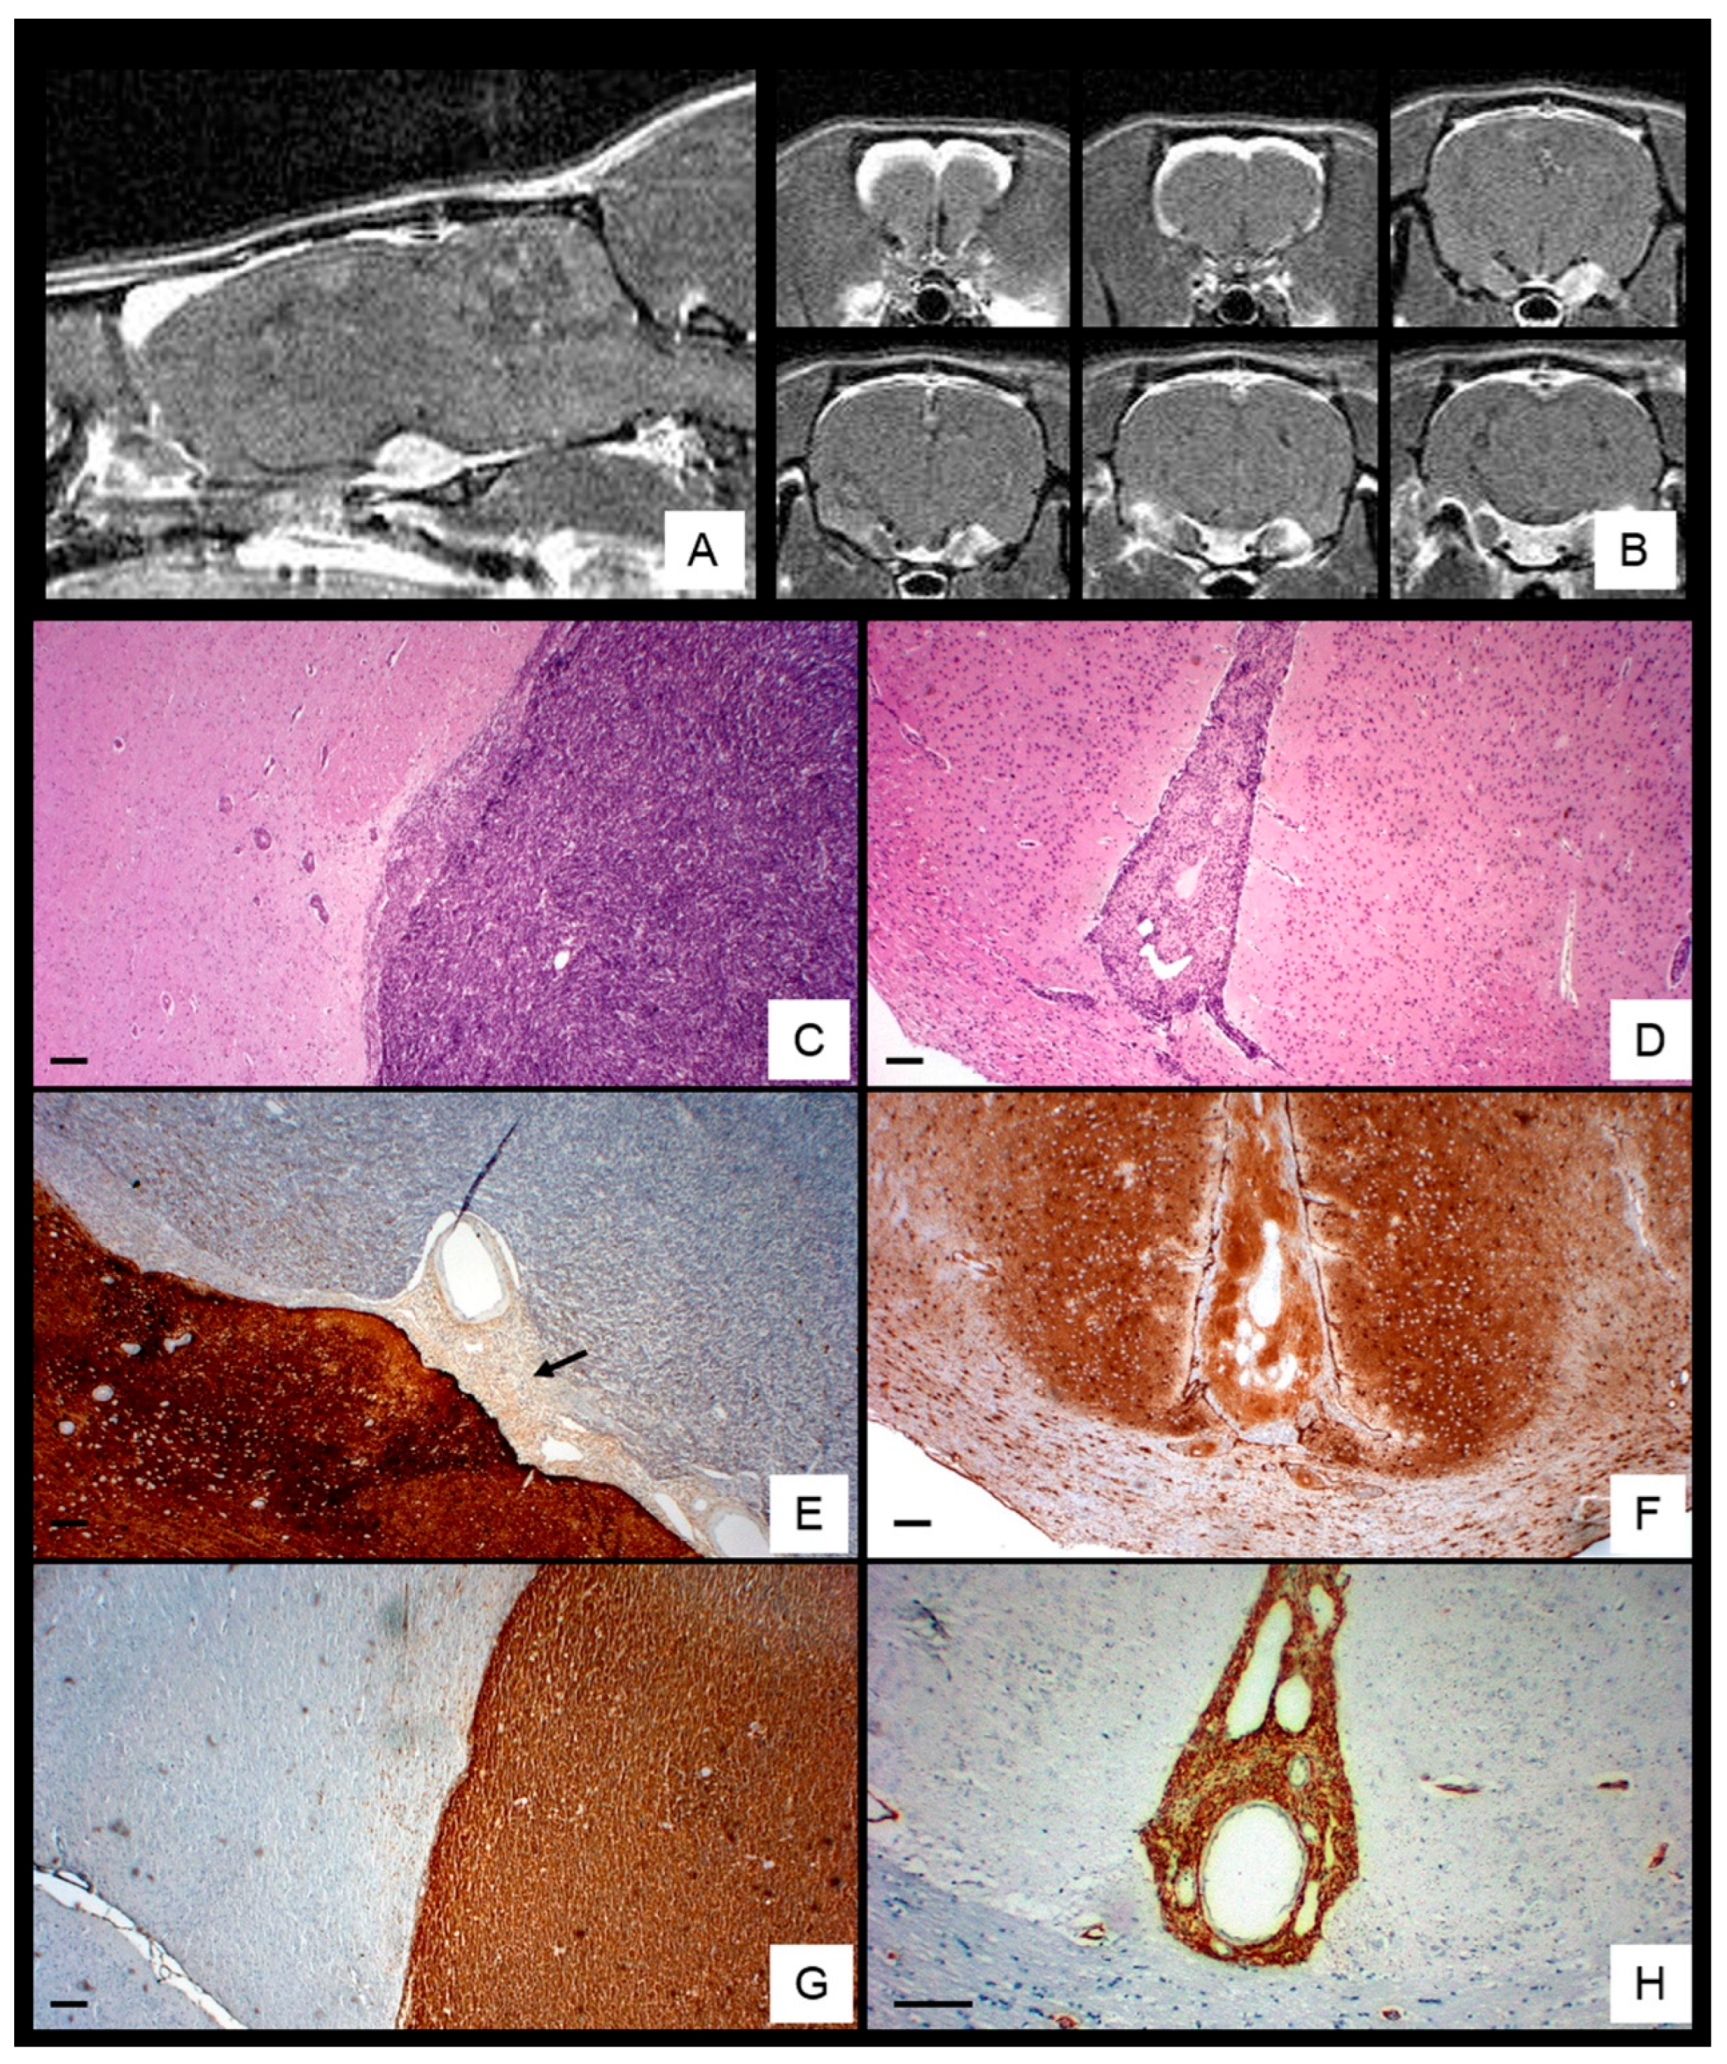

Among 74 ENU-exposed rats (36 females, 38 males), 33.7% developed MPNSTs, with a slight male predominance (M: F 1.3:1) and peak incidence at 6–7 months (

Table 2). MRI revealed enhancing tumors arising from the trigeminal (Gasserian) nerve root, extending along the meningeal sheath and disseminating through subarachnoid and perivascular spaces toward cortical convexities, interhemispheric fissure, and penetrating vessels, causing cortical compression and midline shift (

Figure 1A,B).

Histologically, 17 of 25 analyzed tumors showed basal brain dissemination, characterized by high cellularity, marked pleomorphism, frequent mitoses, hemorrhage and occasionally entrapping Schwann cells (

Figure 1C and

Figure 2A,B). Basal tumors exhibited focal S-100 expression (

Figure 1E and

Figure 2C), strong synaptophysin (

Figure 2D), moderate Ki-67 labeling (

Figure 2E), and scattered p53-positive nuclei (

Figure 2F).

In contrast, eight convexity tumors extended into the interhemispheric fissure and Virchow–Robin spaces, displaying lower cellularity, spindle-shape morphology, rare mitoses, nuclear palisading, and dilated vessels (

Figure 1D and

Figure 2G,L), with diffuse S100 staining (

Figure 1F and

Figure 2J). moderate Ki-67 labeling (

Figure 2K), and low p53 positivity (

Figure 2L). Nestin was consistently expressed in both regions (

Figure 1G,H), whereas GFAP, NF, EMA, EGFR, and NSE were negative. Overall proliferative activity, assessed by Ki-67, was 16.3% ± 8.6%, higher in basal tumors (18.5% ± 8.9%) than in convexity lesions (13.2% ± 7.02%) but not statistically significant (p < 0.05).

Figure 1.

Anatomical and Histological Characterization of ENU-Induced MPNSTs. T1-weighted MRI showing sagittal (A) and coronal (B) sections of a rat head with an ENU-induced MPNST extending from the Gasserian ganglion sheath toward the cortical convexity, producing cortical compression and midline shift. H&E staining reveals tumor spreading at the brain base (C) and within the interhemispheric subarachnoid space (D). S-100 immunolabeling shows focal positivity near the parenchyma (black arrow) (E) and diffuse strong expression at the cortical convexity (F). Nestin immunoreactivity intense in both regions of dissemination sites (G,H). Scale bar: 100 μm.